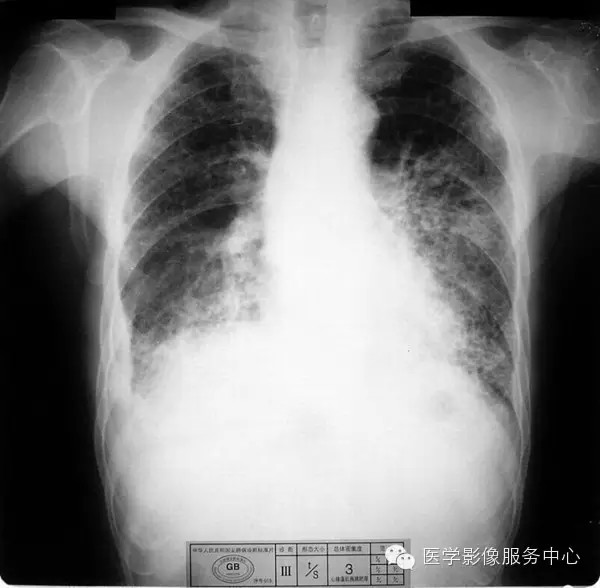

4.3 二期尘肺(Ⅱ)

a)Ⅱ:有总体密集度2级的小阴影,分布范围超过4个肺区;或有总体密集度3级的小阴影,分布范围达到四个肺区。

b)Ⅱ :有总体密集度3级的小阴影,分布范围超过4个肺区;或有小阴影聚集;或有大阴影,但尚不够诊断为Ⅲ者。